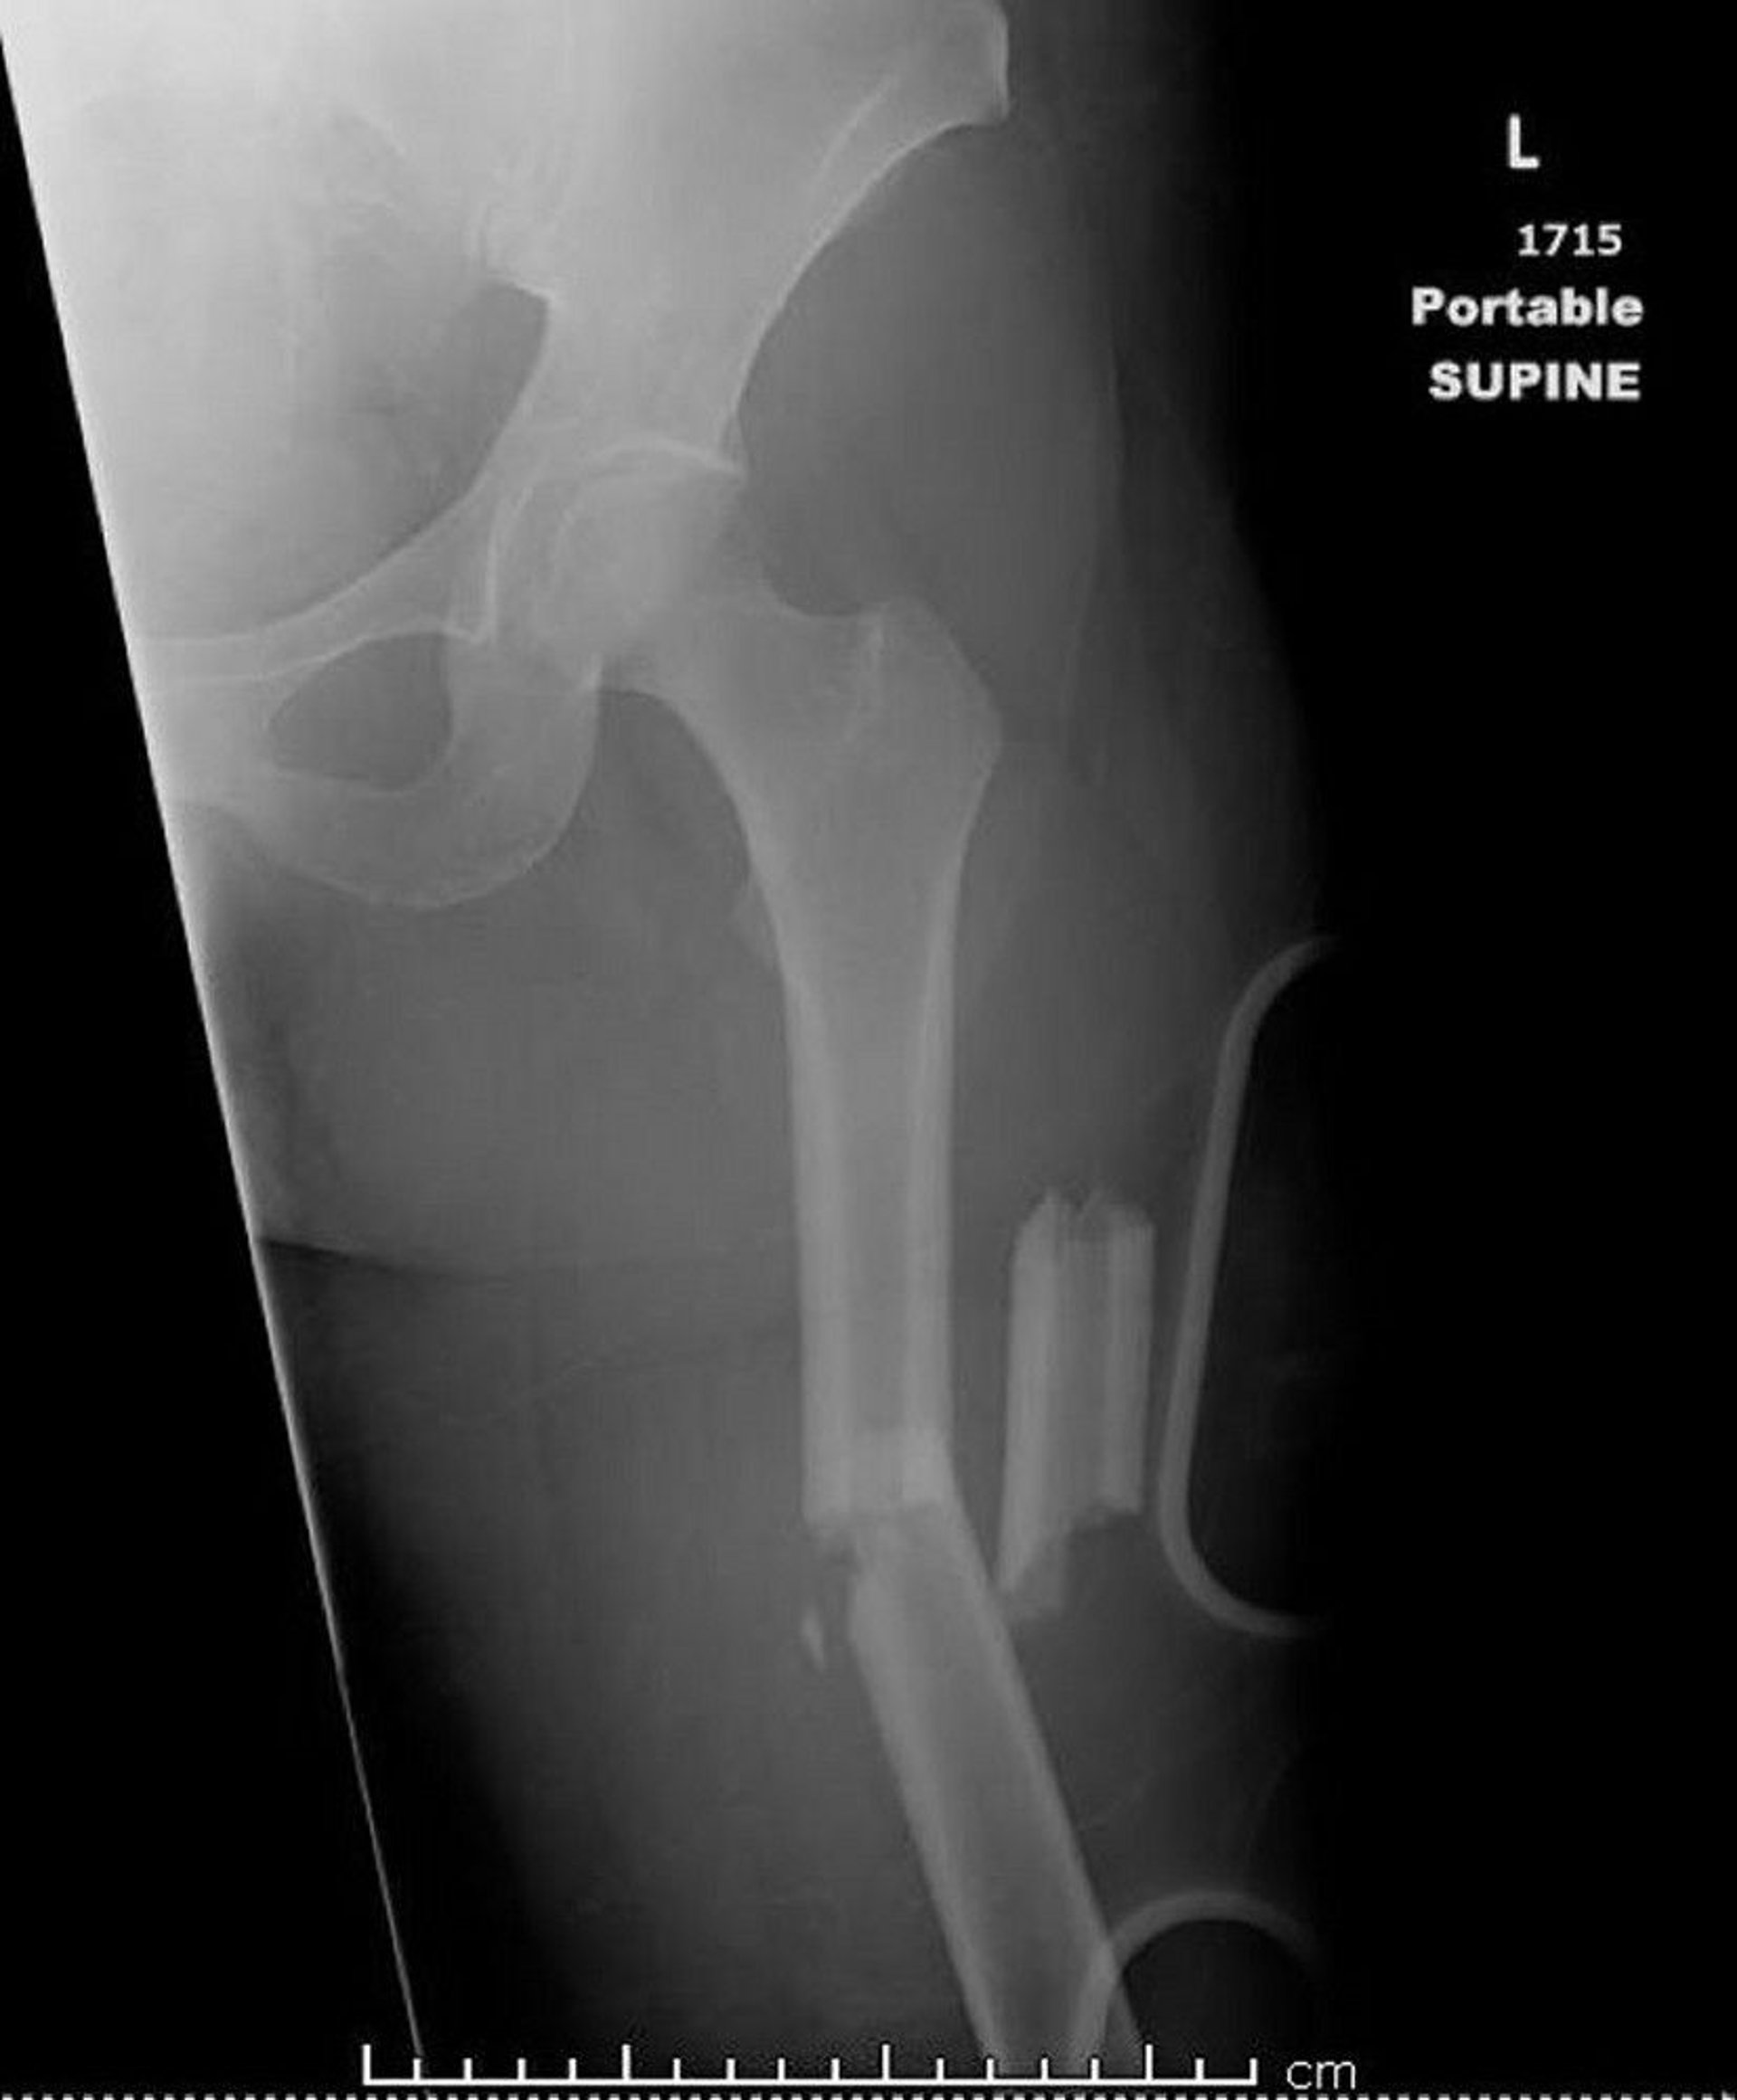

大腿骨骨幹部骨折

この画像には、3カ所以上骨折(粉砕骨折)している大腿骨が写っています。

Image courtesy of Danielle Campagne, MD.